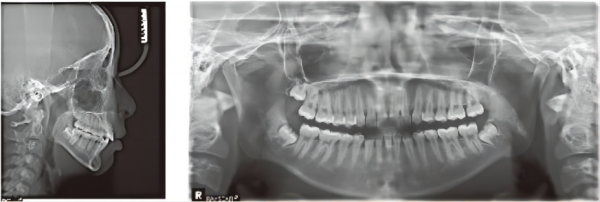

X-ray

Crowding has been relieved, and the Spee curve is leveled. There is a neutral relationship between the bilateral molars and canines, and deep overbite has been corrected.

1. Molar distalization is a key advantage of the VinciSmile treatment. In this case, the patient is not willing to extract the maxillary wisdom teeth, resulting in limitations in distal movement.

2. The resolution of the anterior scissor bite proceeded smoothly because the extent of the scissor bite was not too severe. Therefore, the aligners' inherent splint effect helped reduce occlusal interference during the treatment.

3. VinciSmile demonstrates excellent performance in controlling and calculating minute gaps. The maxillary IPR in this case was within a safe range, highlighting the high precision required by the doctor for accurate IPR control.